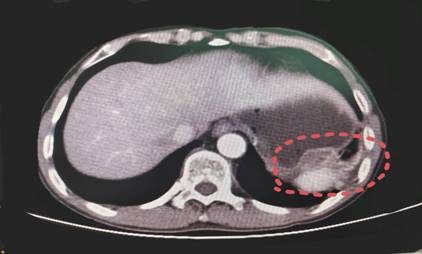

阿辉严格遵照医嘱每日口服4粒伊马替尼,每个月都会到曹高健主任专家门诊进行随访。多次的增强CT复查发现,肿瘤病灶逐步缩小,肝脏的转移灶消失,脾脏、隔肌的侵犯范围缩小,达到了肿瘤学上的PR状态(即:部分缓解状态,图4);且在药物治疗过程中,患者状态良好,基本做到正常起居饮食。

图4 靶向治疗6月后腹部CT影像